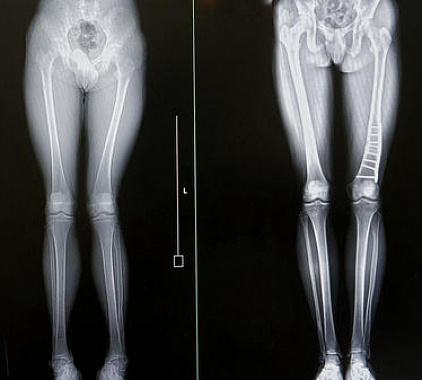

Фотогалерея

Как выглядит перелом кости на рентгене?

Основным инструментальным методом диагностики перелома костей является рентгенография. Процедура позволяет быстро выявить нарушение целостности костных структур и в кратчайшие сроки приступить к нужному лечению. На рентгенограмме можно увидеть место повреждения и его характер, расположение костных фрагментов. Признаками перелома является расхождение, смещение костей, изменение суставной полости.

- оценка успешной консолидации переломов;

- реабилитация после операции;